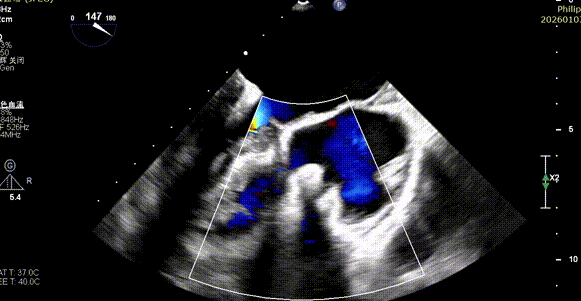

Tricuspid Valve Annuloplasty Stage:Subsequently, via the right internal jugular vein approach, the K-clip® transcatheter tricuspid valve annuloplasty system was delivered to the right atrium. With the assistance of three-dimensional ultrasound stereoscopic views, a 12T clip was successfully implanted at the posteroseptal commissural annulus of the tricuspid valve, and a 14T clip at the anteroposterior commissural annulus, achieving effective constriction of the dilated annulus. Immediate postoperative assessment demonstrated that tricuspid regurgitation was improved from severe (4+) to mild (1+) instantaneously.

1.Intraoperative baseline assessment of regurgitation severity

2.Placement of large sheath and delivery system under ultrasound guidance

3.Steer and rotate the delivery system to target the lesion, and implant the anchor screw via the 3D MPR plane

4.Land the clamping arms after orientation adjustment, and close the clamping arms slowly

5.Perform the same procedure for the second clip; the clip morphology is stable under 3D imaging